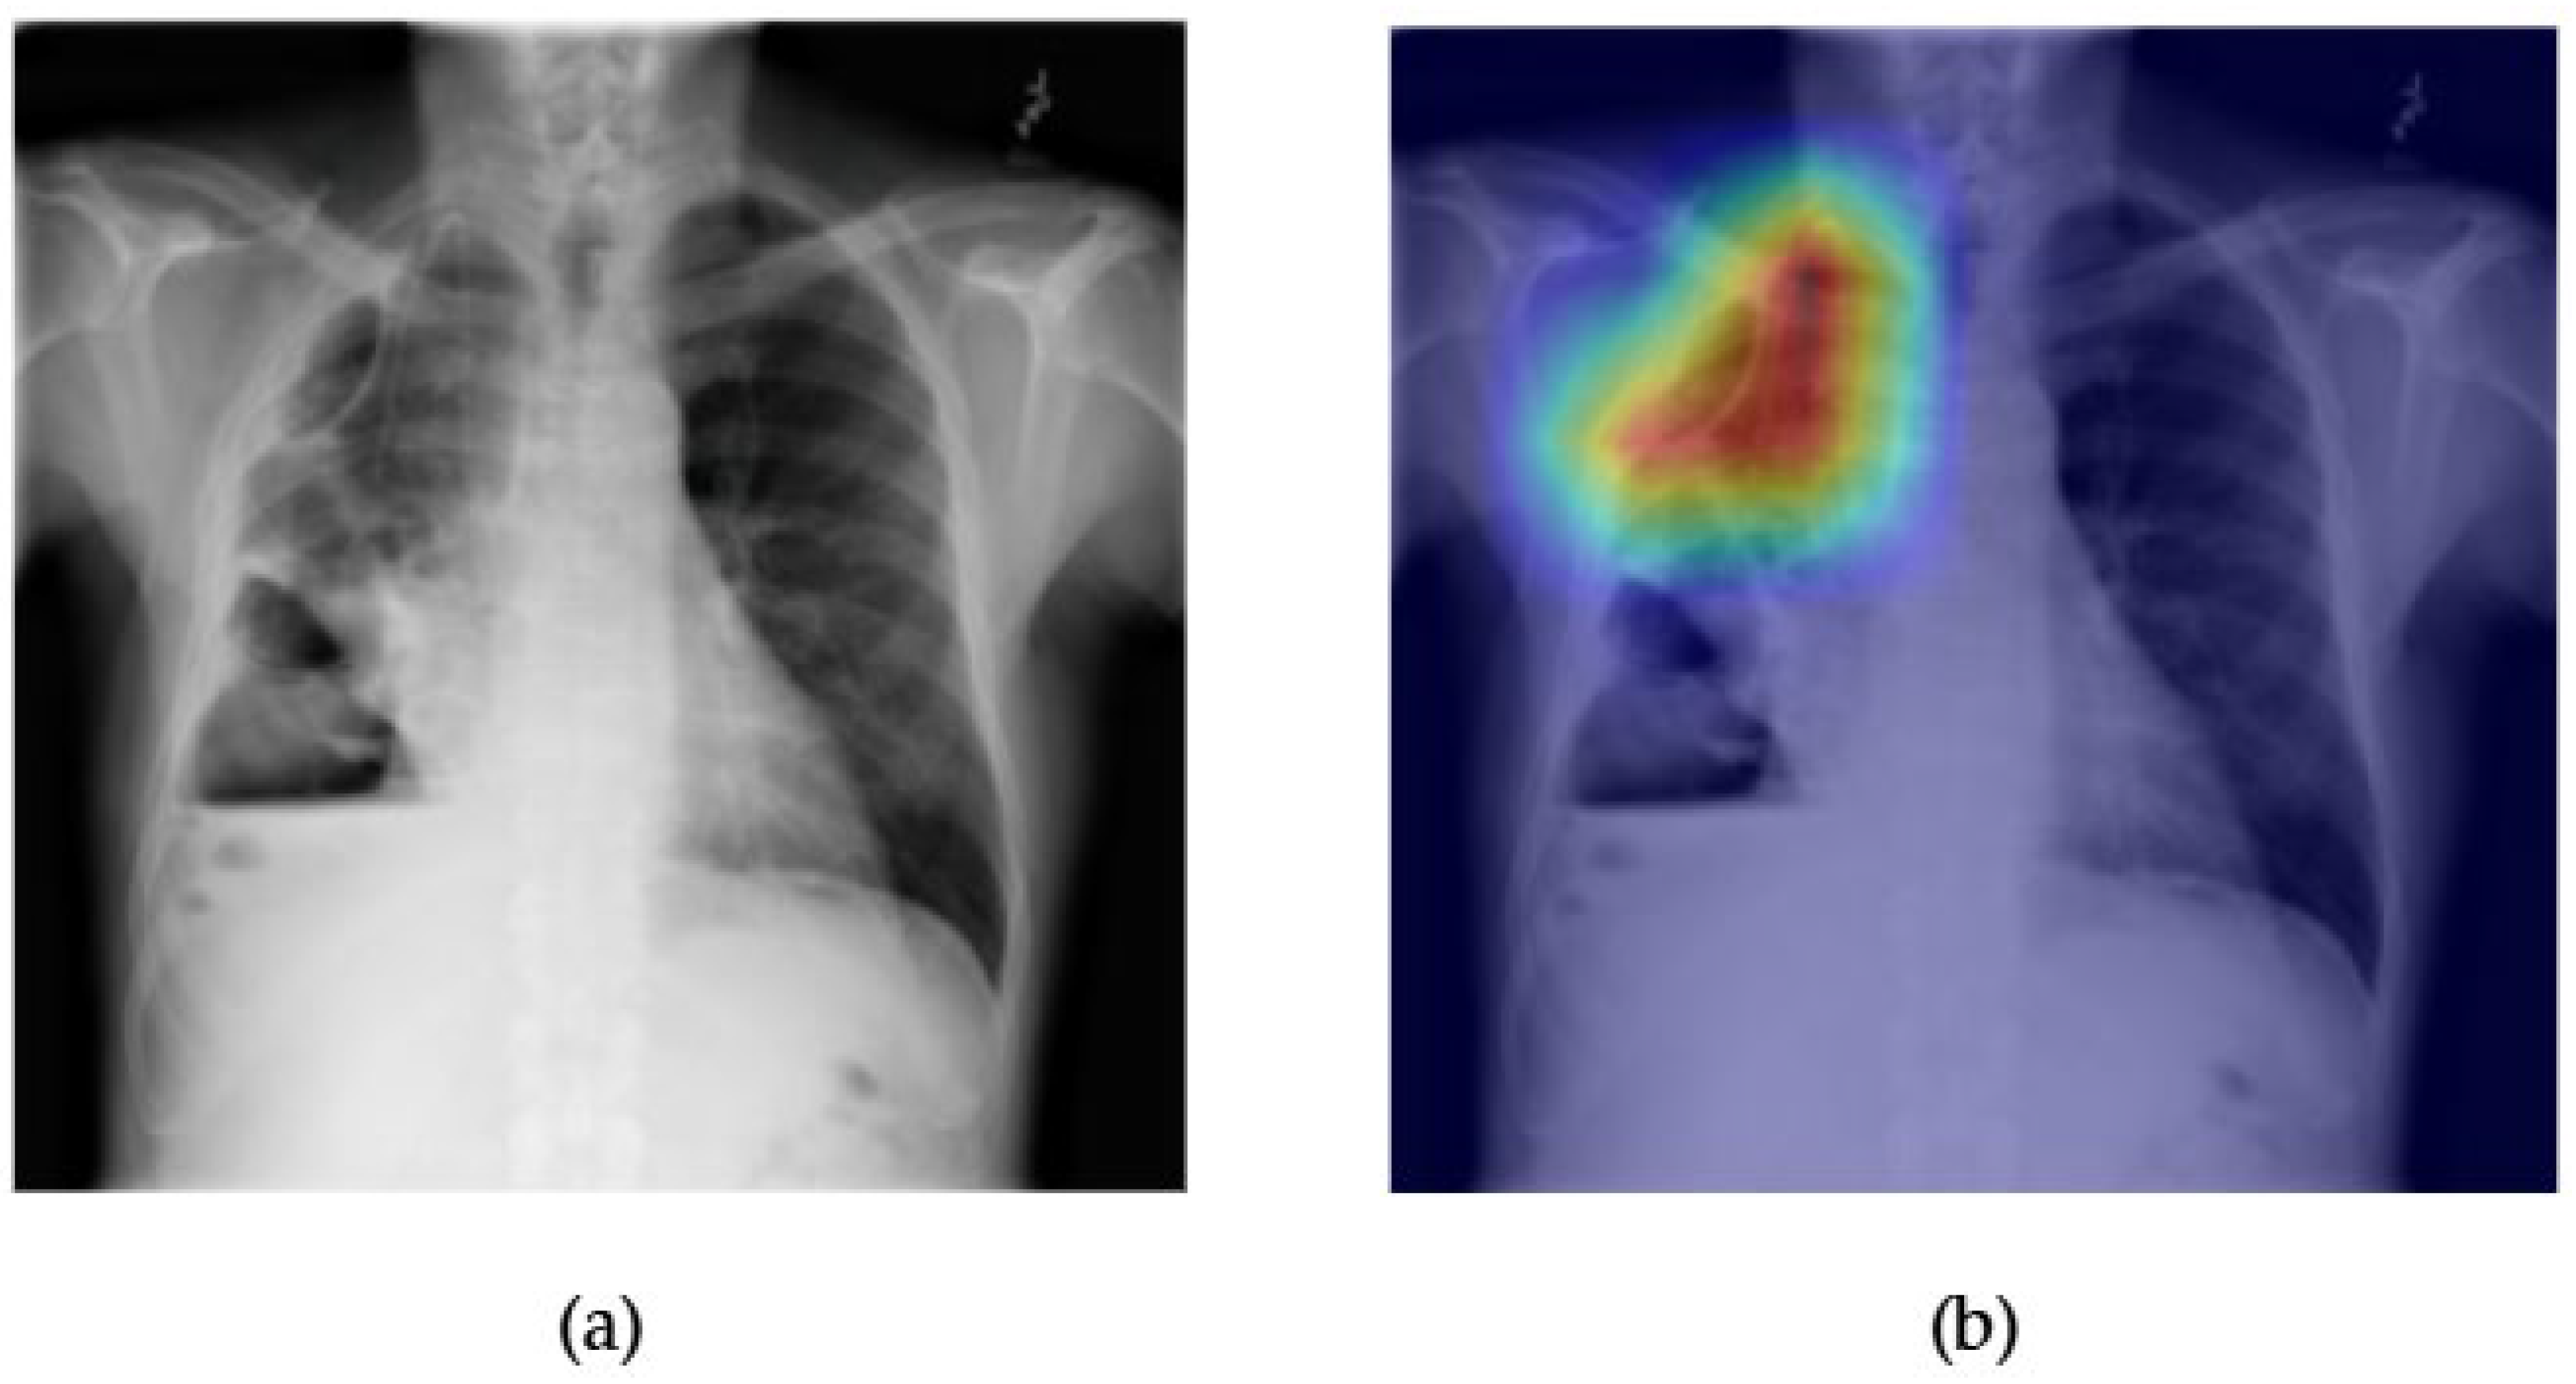

- Although our Grad-CAM-based explainability provides useful localization cues, it is inherently limited by its post hoc nature and reliance on gradient flow from the final convolutional layers. Future research could incorporate advanced interpretability techniques such as Layer-wise Relevance Propagation (LRP), Integrated Gradients, or attention rollouts in Transformers, which may offer a more complete understanding of model reasoning.